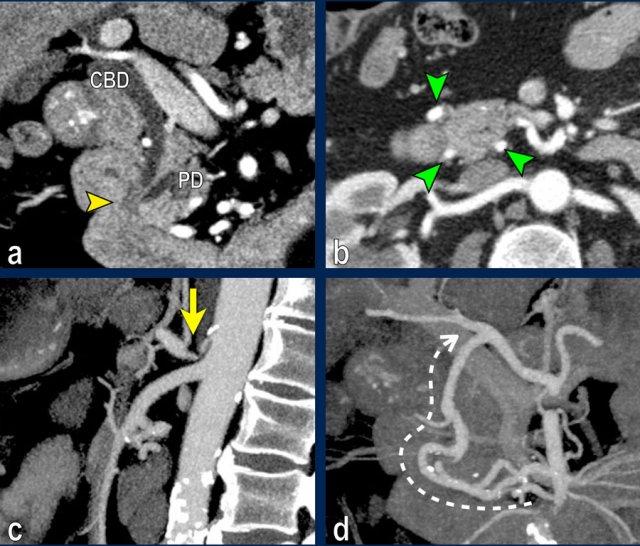

Hình tái tạo mặt phẳng đứng ngang (a) cho thấy một khối u nhỏ ở vùng bóng Vater (đầu mũi tên), gây tắc nghẽn cả ống mật chủ (CBD) và ống tụy (PD). Khi không có xâm lấn tại chỗ, tổn thương này được xem là có thể cắt bỏ được.

Tuy nhiên, hình CT axial (b) cho thấy phì đại của cung động mạch quanh tụy (các mũi tên), gợi ý mạnh hẹp đáng kể thân tạng.

Hẹp thân tạng được thể hiện trên hình MIP mặt phẳng đứng dọc (mũi tên trong c).

Dòng máu bàng hệ đến động mạch gan qua cung động mạch tụy-tá tràng (mũi tên nét đứt) được quan sát rõ trên hình MIP mặt phẳng đứng ngang (d).